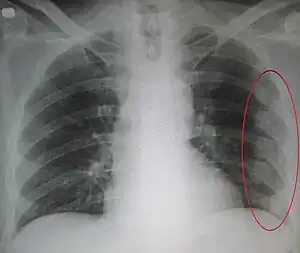

An X ray showing multiple old fractured ribs of the person's left side as marked by the oval.

Plain X-rays often pick up displaced fractures but often miss undisplaced fractures.[13] CT scanning is generally able to pick up both types of fractures.[13]